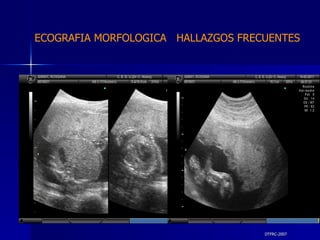

DTFRC-2007 ECOGRAFIA MORFOLOGICA  HALLAZGOS FRECUENTES   SISTEMA NERVIOSO CENTRAL TOTAL  8  26 % 1 HIDROCEFALIA 2 VENTRICULO MEGALIA 4 QUISTE DE PLEXO COROIDEO 1 ANENCEFALIA

DTFRC-2007 ECOGRAFIA MORFOLOGICA  HALLAZGOS FRECUENTES   GENITOURINARIA DISPLASIA RENAL MULTIQUISTICA  3 HIDRONEFROSIS  2 QUISTE DE OVARIO FETAL  1 SISTEMA DIGESTIVO DILATACION INTESTINAL  2  SISTEMA ESQUELETICO   PIE BOT  2  20 % 6 % 6 %

DTFRC-2007 ECOGRAFIA MORFOLOGICA  HALLAZGOS FRECUENTES   OTROS HIGROMA QUISTICO  2 ENFERMEDAD ADENOMATOSA PULMONAR  1 ARTERIA UMBILICAL UNICA  2 HIDROPS FETAL NO INMUNE  1 QUISTE DE CORDON UMBILICAL  1 ALTERACION DE LIQUIDO ANMIOTICO  2 SINDROME TRAFUSIONAL FETO FETAL 1 LABIO LEPORINO  2 TOTAL  12  42 %